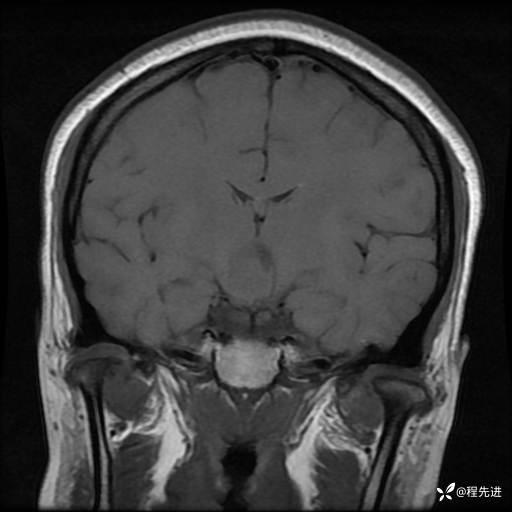

MRI平扫+增强:

T1+C: